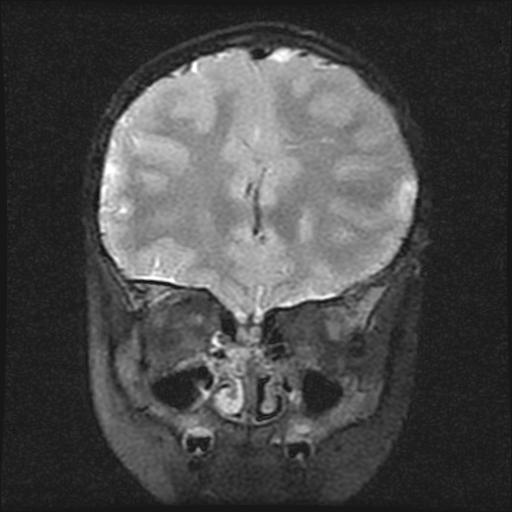

6岁小儿,左侧视神经瘤术后。现左侧视力减退。